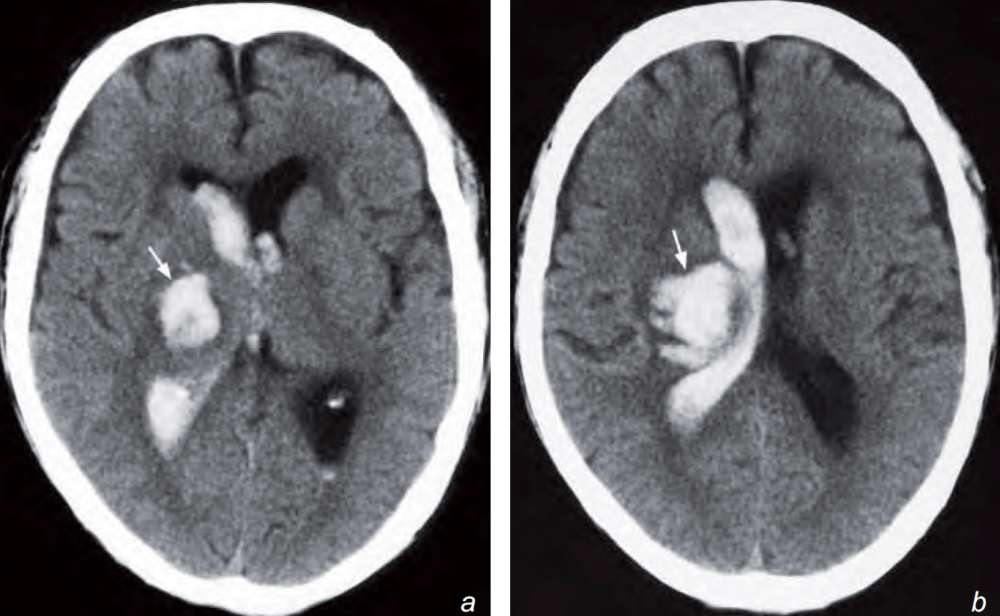

There is an acute intraparenchymal haematoma in the right thalamus and lentiform nucleus with intraventricular extension into the lateral ventricles.

Non-contrast axial CT scan showing a right thalamic and lentiform nucleus haemorrhage (arrow) with extension of blood into the lateral ventricle. The location is typical for a hypertensive haemorrhage.